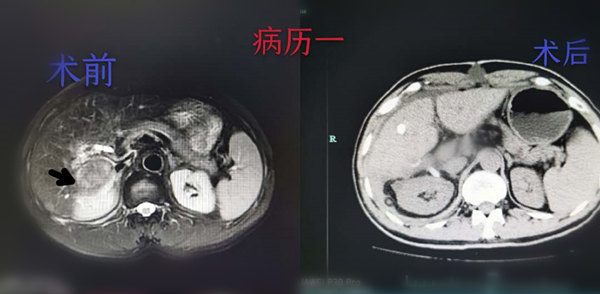

市人民医院成功完成2例凶险位置的复发性肝脏肿瘤切除手术 |